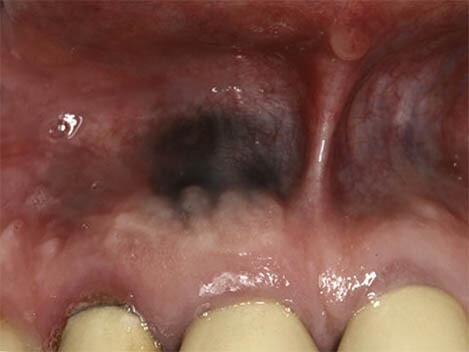

What Causes a Black Spot on Your Gums?

First, we recommend taking a moment to breathe and relax. According to the Oral Cancer Foundation, dark spots rarely indicate a serious condition like cancer and are usually benign. Spots in the mouth are often not fully black but may appear that way as they can be hard to see. We’re here to help walk you through the causes of dark spots in your mouth and what they mean.

Causes of Dark Spots on Gums

Oral conditions like dark spots on your gums have various causes and can be challenging to diagnose. These spots can either be harmless or the result of an underlying disease, so it's essential to speak to your doctor if you believe you have any symptoms.

What exactly causes black spots on your gums? There are two categories of answers: those with internal causes and those with external causes.

Did you know: Internal causes are called endogenous and external causes are called exogenous.

Internal Causes

Internal pigments that cause skin colour changes can also modify your gums' colour to black, grey, blue, or brown. Blood vessels can even dysfunction or rupture, leading to discolouration.

Melanin can be altered by a variety of diseases and disorders that affect the production of this pigment. Cells in your body that produce melanin are called melanocytes.

Tuberculosis and Addison's disease can affect your adrenal glands and cause changes in pigmentation.

HIV, also called the human immunodeficiency virus, can lead to pigmented lesions in the mouth.

According to a research article published in the Journal of Indian Academy of Oral Medicine and Radiology, haemangiomas are most common soft tissue benign tumours, composed of blood vessels, and occur in the head and neck region (60%) and less commonly in the oral cavity; oral cavity if affected involves gingiva followed by the lips, tongue and palate.

External Causes

Exposure of your mouth to pigment produced outside the body can lead to discolouration in the form of dark or spots on the gums. Sources outside the body can also affect your body's production or regulation of pigment or iron, leading to a change in colour. These black dots can be caused by:

Drugs (prescription, over-the-counter and illegal)

Smoking and tobacco products

Trauma to the face or mouth

Heavy metals

Injury from graphite pencil

An old filling (also known as a dental amalgam)pushing into the gums

Oral Cancer

In rare cases, benign lesions that don't require treatment may transform into oral malignant melanoma, a type of oral cancer. A doctor will look at a range of factors to see if the lesion qualifies as melanoma. According to a research article published in the Journal of Indian Academy of Oral Medicine and Radiology, melanoma constitutes only 3–5% of all cutaneous malignancies, and oral melanoma is an aggressive neoplasm which accounts for less than 0.5%.

If you believe you have oral cancer symptoms, we recommend leaving the diagnosis up to the professionals and speaking to your doctor. If you exhibit symptoms, they may perform a biopsy (laboratory tests of your tissue) to confirm melanoma.

Remember that cancer is a rare cause of any dark spots in your mouth. A more benign explanation is much more likely, so don't stress. You've done a great job informing yourself of the possible causes, so be sure to make the next step for success and schedule an appointment or regular check-ups with your doctor.